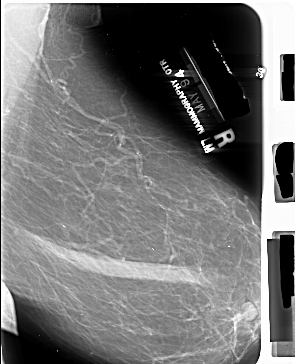

A_1014_1.RIGHT_CC

RIGHT_CC LINES 6886 PIXELS_PER_LINE 4456 BITS_PER_PIXEL 16 RESOLUTION 42 NON_OVERLAY